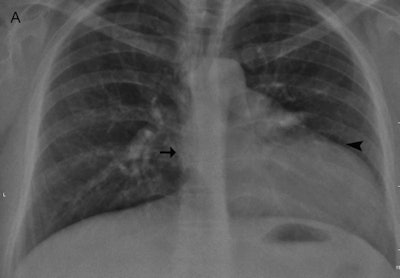

In one case the authors encountered at their hospital, an otherwise healthy 35-year-old woman was referred for ovarian cyst surgery. A chest radiograph demonstrated marked displacement of the cardiac silhouette to the left with flattening and elongation of the left ventricular contour (Snoopy sign) and obliteration of the right cardiac border (see figure).

Above A: Frontal chest radiograph shows displacement of the cardiac silhouette to the left, with flattening and elongation of the left ventricular contour (arrowhead) and obliteration of the right cardiac border (arrow). Below B: Gradient-recalled echo axial MRI shows complete absence of the left pericardium (arrowheads), with obliteration of pericardial fat and a partial right-sided pericardium (arrows) seen as a dark, thin stripe sandwiched between the epicardial and pericardial fat. Images courtesy of Dr. Stavroula Theodorou and Dr. Daphne Theodorou, PhD.A cardiac MRI scan was performed to investigate cardiac levoposition and other associated abnormalities. Axial gradient-recalled echo (GRE) MR images showed a partial right-sided pericardium, seen as a dark stripe between the epicardial and pericardial fat, and complete absence of the left pericardium with obliteration of pericardial fat.